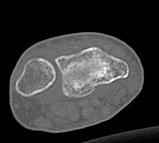

Уважаемые коллеги.Прошу обсудить случай лечения перелома дистального метаэпифиза лучевой кости. Ситуация скандальная и крайне неблагоприятная. Больная с патологической обстоятельностью мышления, склонностью к сутяжничеству, патологическими умозаключениями, не поддающимися коррекции (см. психиатрию, правда офиц. диагноза нет). В данном случае есть ряд ошибок с нашей стороны, прежде всего в отношении качества ведения документации (за что получил административное взыскание, по делом мне дураку). В остальном- придерживались в лечении подхода классический советской школы. Так как умную операцию…… сами знаете… 15.12- перелом луча в Москве. Там же репозиция, гипс. Дальнейшее лечение у нас в ЦРБ. 20.12.- вторичное смещение в гипсе21.12- под внутривенным наркозом- репозиция, гипсовая лонгета. Дальше начинается самое интересное. После репозиции больная заявила, что я (репозицию делал я) порвал ей все связки в суставе, посинел у нее 5 палец, якобы я за него тянул и т. д. На самом деле на 2 сутки после репозиции рука немного отекла и было незначительное сдавление гипсом, который был ослаблен. Дальнейшее лечение консервативное. Через 6 недель- гипс снят, назначено ЛФК. Пациентка крайне недовольна. Говорит, что на снимке у нее выступает кость, я ей сломал руку и.т.д. В общем началось. Пациентка прочитала в интернете наверное все, что есть по данной травме.По заключениями рентгенологов и консультанта из КДЦ областной больницы - стояние отломков допустимое. Объективно говоря- снижена высота лучевой кости, диастаз лучелоктевого сочленения, и не сросся шиловидный отросток. однако на РКТ при сравнении с другой стороной- разница незначительная. Дальше в одной из больниц нашей области и одной из больниц Москвы (вроде бы КГБ 53) врачи сказали, что репозиция сделана плохо. Нужна операция (восстановить длину лучевой кости), даже один из них предложил РЕДРЕССАЦИЮ (хи-хи) с наложением аппарата Илизарова. Что это для данной больной- радость неописанная. (см. описание психического статуса). Ничем другим, кроме зарабатывания дешевого авторитета объяснить данный факт не могу.Кстати, у больной еще нейропатия локтевого нерва.Для разрешения конфликта больная направлена на консультацию в ЦИТО на 03.03.11.

Теперь вопросы: 1.Прошу объективно оценить качество нашей репозиции на момент 21.12. (неужели так плохо?). Что на снимках при снятии гипса- сам вижу. 2. сравнить снимки РКТ (с двух сторон)- так ли велико укорочение лучевой кости и лучелоктевой диастаз. 3. Ваши мнения, в отношении целесообразности оперативного лечения учитывая ВСЕ вышеизложенное. 4. На всякий случай для суда- мог ли я тракцией в 2- 3 кг за 1 и 2 пальцы под внутривенным наркозом неправильно вколотить отломки и травмировать локтевой нерв. Кстати, в США если врач пациенту говорит, что его плохо лечили- то этого врача лишают лицензии. У нас наооборот- обгадить другого милое дело. И это процветает. От себя же могу сказать, что никто в нашем отделении так не поступает. Коллеги, будьте осторожны в своих высказываниях. От осложнений и ошибок никто не застрахован. А в данном случае многое будет зависеть от заключения консультантов поликлиники ЦИТО, куда больная направлена областным травматологом на 03.03 для решения вопроса о дальнейшей тактики лечения. С уважением ко всему травматологическому сообществу Дедок Михаил.